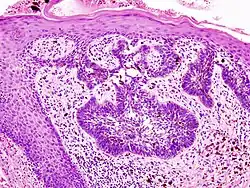

H&E stain

Main types of staining seen on H&E stain

Hematoxylin and eosin stain (or haematoxylin and eosin stain or hematoxylin–eosin stain; often abbreviated as H&E stain or HE stain) is one of the principal tissue stains used in histology.[1][2][3] It is the most widely used stain in medical diagnosis[1] and is often the gold standard.[4] For example, when a pathologist looks at a biopsy of a suspected cancer, the histological section is likely to be stained with H&E.

H&E is the combination of two histological stains: hematoxylin and eosin. The hematoxylin stains cell nuclei a purplish blue, and eosin stains the extracellular matrix and cytoplasm pink, with other structures taking on different shades, hues, and combinations of these colors.[5][6] Hence a pathologist can easily differentiate between the nuclear and cytoplasmic parts of a cell, and additionally, the overall patterns of coloration from the stain show the general layout and distribution of cells and provides a general overview of a tissue sample's structure.[7] Thus, pattern recognition, both by expert humans themselves and by software that aids those experts (in digital pathology), provides histologic information.

Hematoxylin principally colors the nuclei of cells blue or dark-purple,[6][15][14] along with a few other tissues, such as keratohyalin granules and calcified material. Eosin stains the cytoplasm and some other structures including extracellular matrix such as collagen[5][7][14] in up to five shades of pink.[8] The eosinophilic (substances that are stained by eosin)[5] structures are generally composed of intracellular or extracellular proteins. The Lewy bodies and Mallory bodies are examples of eosinophilic structures. Most of the cytoplasm is eosinophilic and is rendered pink.[10][15] Red blood cells are stained intensely red.